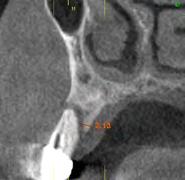

maxilares, lo que apunta a la existencia de una atrofia vertical ósea excesiva en esta área que pretende ser rehabilitada con implantes dentales (Figura 5). A mayor aumento vemos la fractura radicular de la pieza 13 que ha generado el defecto circunferencial (Figura 6) y en el cone beam de planificación se constata y además se pone de manifiesto la dimensión del defecto óseo y el volumen óseo residual a nivel palatino de 2 mm (Figura 7).

Figura 5. Radiografía inicial del paciente. En ella observamos el defecto crateriforme del diente 13 y una neumatización excesiva de ambos senos maxilares en el maxilar posterior donde se pretenden realizar implantes dentales. Figura 6. Imagen en detalle de la pieza 13. En esta imagen cercana podemos observar una fractura vertical evidente en el área del ápice ya en este tipo de prueba radiológica. Figura 7. En el cone-beam de planificación se objetiva la fractura y el defecto crateriforme con pérdida de la tabla vestibular completa y un remanente óseo a nivel palatino de 2 mm para la posterior inserción de un nuevo implante.